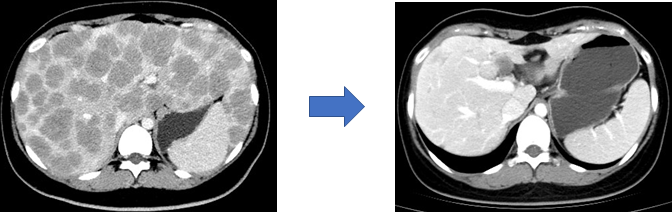

文献报道约60%的神经内分泌肿瘤发现时已属中晚期,直接手术治疗效果不佳。目前多采用药物转化治疗。经过药物治疗后肿瘤负荷降低、范围及体积缩小,在联合手术治疗可进一步改善患者预后(图7,8)。常用的转化治疗手段包括靶向药物治疗、化疗、介入治疗及PRRT等。

图7

22岁女性患者,2018年瑞金医院就诊,诊断胰腺神经内分泌肿瘤G3伴弥漫肝转移。经瑞金医院胰腺神经内分泌肿瘤多学科团队会诊明确诊断并予以卡培他滨联合替莫唑胺口服化疗,服药12个月肿瘤达到完全缓解,原发病灶及转移病灶消失,目前肿瘤持续缓解。左图为口服化疗前影像(弥漫肝转移),右图为药物治疗12个月的影像(转移病灶完全缓解)。